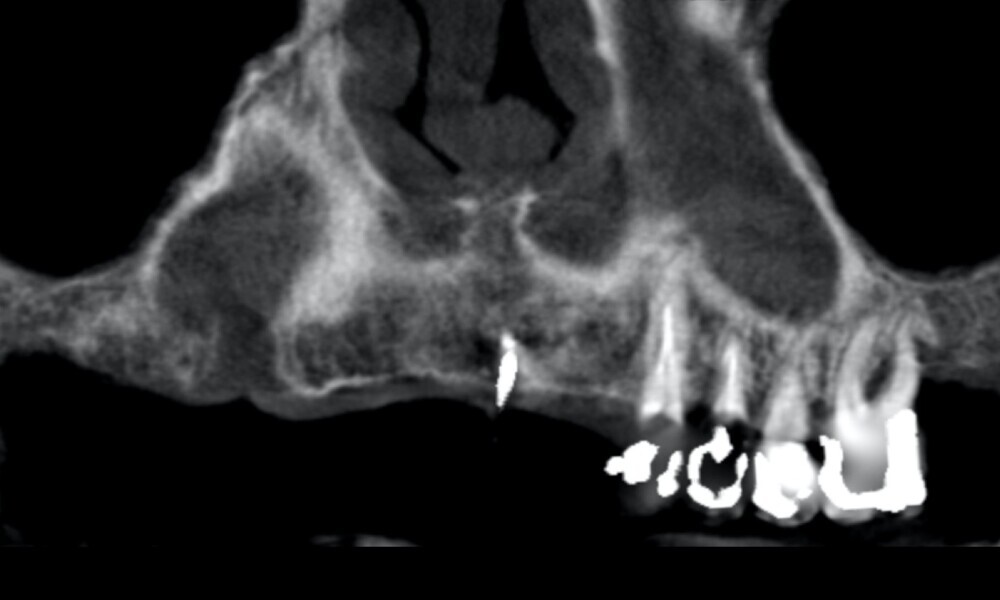

Extra-oral examination showed no significant abnormalities. The patient presented with a medium smile line (Figs. 1–3). The intra-oral examination revealed a fixed bridge spanning teeth #23–26 to which the removable metal partial denture attached (Fig. 4). Teeth #22–17 had been extracted a long time before, and the ridge in this region had healed. No plaque or inflammation was observed. The teeth exhibited mild to moderate attachment loss, but no endodontic or periodontic lesions or root fractures were observed (Figs. 5–8). Analysis of the panoramic radiograph indicated sufficient vertical and horizontal bone availability and adequate bone quality; therefore, there was no need for guided bone regeneration (Fig. 9). According to the International Team for Implantology’s SAC classification, the case was categorised as advanced to complex.

Four months later, we proceeded with the final prosthetic procedure based on clinical and radiographic evidence confirming osseointegration. The case was completed using Straumann RevEX scan bodies for a full monolithic design with a completely digital workflow. First, an intra-oral scan of the opposite arch was taken, followed by an intra-oral scan with the screwed-in temporary abutments. An intra-oral bite scan and an intra-oral scan of the soft tissue with the screw-retained abutments in place were then taken. The reverse scan bodies were attached to the provisional prosthesis, which was scanned extra-orally. Next, the prototype and verification jig were designed, followed by the milling of the prototype and verification jig (Figs. 45 & 46).

The delivery of the final prosthesis was then performed, and the aesthetics, occlusion and function were verified (Figs. 51–55). The panoramic control radiograph showed that all measurements were within expected ranges (Fig. 56).